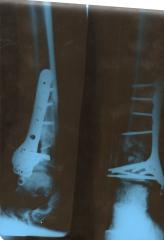

Noha po operaci v Liberci s naloženou zevní dlahou

Aplikace dlahy na kost ve vrchlabské nemocnici